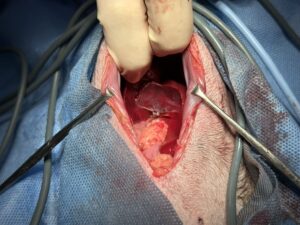

血液検査にて肝酵素の上昇や、エコーにおいて胆泥貯留が認められ胆嚢粘液嚢腫・胆嚢炎の疑いがあったため手術を行いました。

中央に見えているのが胆嚢です

脾臓にも病変が認められたため摘出

胆嚢:慢性胆嚢炎および軽度胆嚢粘液嚢腫

脾臓:結節性過形成

胆嚢の一部が出血により消失しており、内容物が腹腔内へ漏出する可能性が高い状態でした。

今回は未然に防ぐことができ、術後の経過も大きく問題はありませんでした。